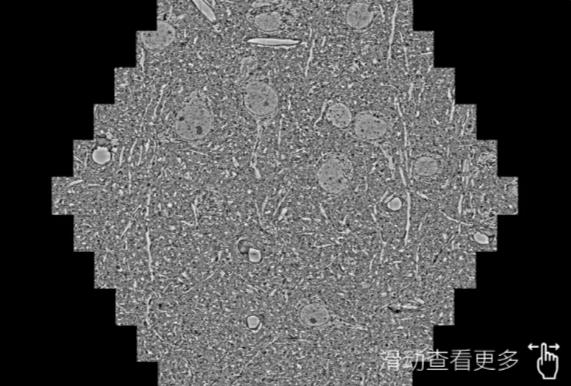

鼠脑切片。左图使用长春蔡司长春扫描电镜MultiSEM706对165μmx143pm面积区域成像,耗时仅需1.5秒。右图为鼠脑切片中30μm区域放大效果。样品由芝加哥大学B.Kasthuri提供。

使用蔡司高速长春扫描电镜MultiSEM对1mm²人脑皮层组织进行高分辨成像,并对其中的各种细胞结构进行三维重构分析。左图展示了2x3mm²组织平面中锥体神经元的三维重构效果。右图显示了局部体积神经元三维重构。图像由哈佛大学chtman实验室提供,渲染图由D. Berger 制作。